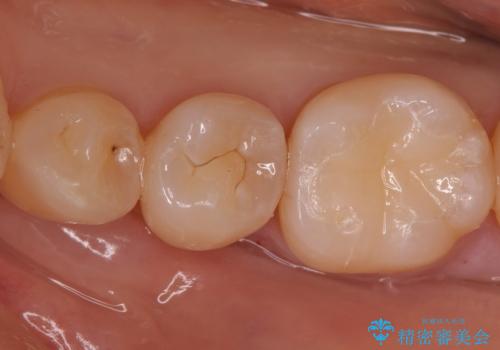

- 奥歯の樹脂の色が気になるとのことで来院されました。

変色しない材料での治療をご希望されたためセラミックインレーでの治療をしていくこととなりました。

- 左下6 セラミックインレー 77,000円×1本費用は治療当時の料金となります

継ぎ接ぎになった樹脂の詰め物から一塊のセラミックインレーに置き換えることで着色や二次う蝕のリスクを抑えます。